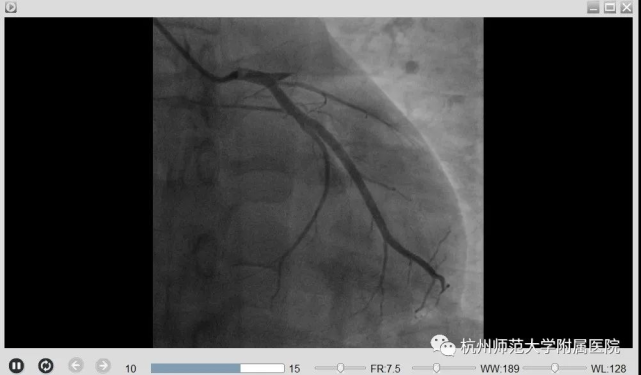

刘主任立刻启动胸痛中心绿色通道,通知患者家属后,刘主任带领胸痛团队立即将患者送至导管室,经过冠脉造影证实,患者前降支血管(为心脏收缩的主要功能血管)完全闭塞,符合De-Winter综合征的表现,立即予以开通闭塞的血管,植入支架1枚,小方心脏血管血流恢复,胸痛症状明显缓解,血压心率逐渐平稳下来。

手术前后对比图